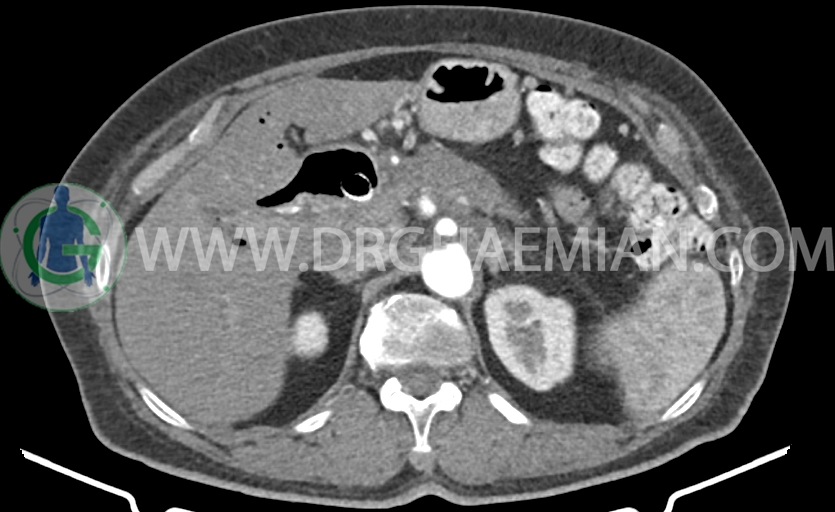

در سی تی اسکن اسپیرال شکم و لگن با و بدون کنتراست خوراکی و وریدی- پروتکل پانکراس (مولتی دیدکتور 16 با مقاطع ظریف و بازسازی های ساژیتال و کرونال) :

– Stent در CBD

–دانسیته هوا در CBD و مجاری صفراوی داخل و خارج کبدی و کیسه صفرا (ثانویه به دستکاری)

–مجاری صفراوی داخل کبدی مختصر دیلاته است.

-CHD دیلاته (20mm)

– توده هیپودنس ill – defined با حداکثر دیامتر تقریبی 50mm در ناحیه گردن و پروگزیمال body پانکراس( بدون تغییر قابل توجه در سایز نسبت به سی تی اسکن 1401/9/17 )

همراه با encasement در SMA ،SMV، شریان اسپلنیک، شریان هپاتیک و پروگزیمال ورید پورت (بدون تغییر نسبت به سی تی اسکن 1401/9/17)

– اتروفی دیستال پانکراس (بدون تغییر نسبت به سی تی اسکن 1401/9/17)

– شواهد فوق مطرح کننده ضایعات malignant پانکراس ( آدنوکارسینوم ) می باشد که بر اساس معیار های

NCCN ،localy advanced و unresectable می باشد.